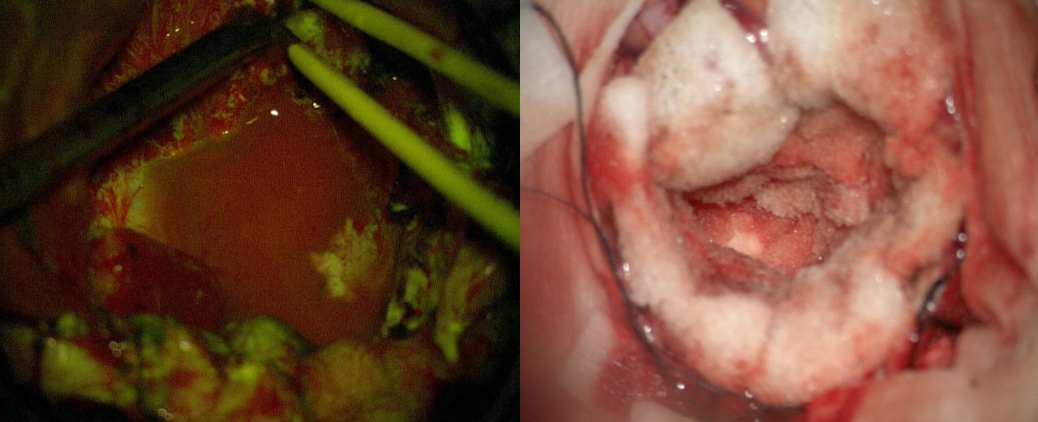

术中荧光染色情况

术中肿瘤荧光染色及止血情况